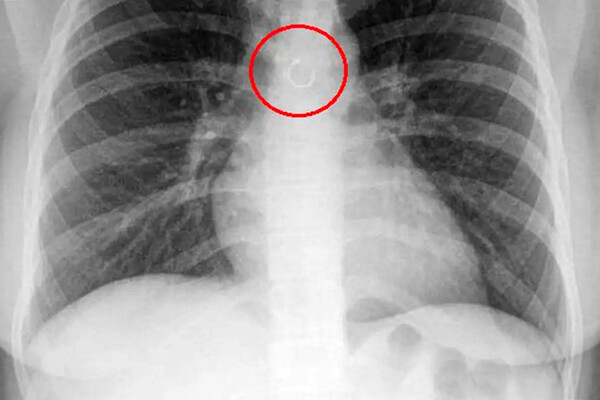

Во время обследования выяснилось, что украшение из пирсинга в носу каким-то образом оказалось глубоко в дыхательных путях девушки и застряло в легких. Металлический элемент находился всего в полумиллиметре от аорты, что могло привести к опасным последствиям, добавили медики.